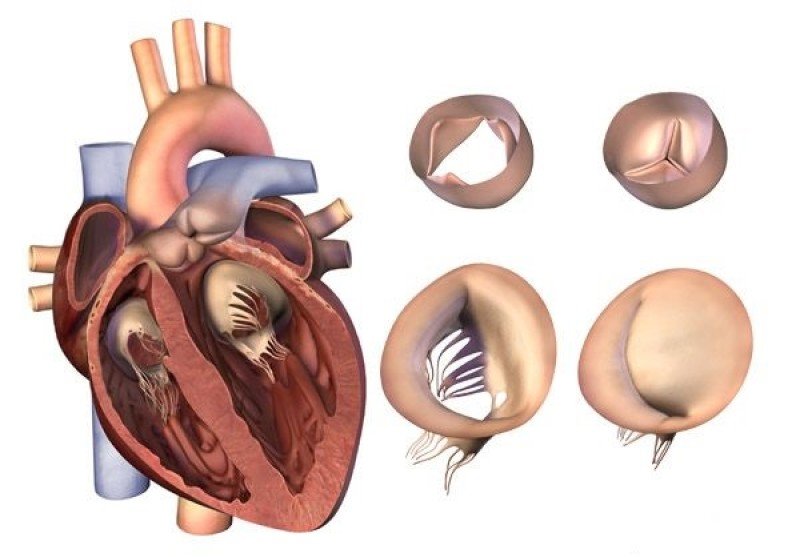

- Изучение клинико-патогенетических особенностей формирования аортального стеноза в зависимости от морфологии аортального клапана.

- Оценка потенциальных генетических предикторов кальциноза аортального клапана.

Иртюга, О.Б. Способ прогнозирования риска развития аортального стеноза у пациентов с бикуспидальным аортальным клапаном и дилатацией восходящего отдела аорты. /Иртюга О.Б., Жидулева Е.В., Пугина М.Ю., Шадрина У. М., Бабакехян М.В. // Свидетельство о государственной регистрации изобретения. Заявка № 2023115962 от 19.06.2023 дата регистрации от 27.08.2024

Иртюга О.Б. выступила с докладом, посвященным патогенезу бикуспидального аортального клапана и его связи с аортальным стенозом и аневризмой аорты на Российско-Индийском симпозиуме «Новые технологии диагностики и лечения патологии аорты и аортального клапана».

Также представила доклад на тему «Место медикаментозной терапии в лечении аортального стеноза» в рамках симпозиума «Новая эра в диагностике и лечении аортального стеноза».

Irtyuga, O. NOTCH1 mutations in aortic stenosis association with osteoprotegerin/RANK/RANKL / Irtyuga O., Malashicheva A., Zhiduleva E. [et al.] // BioMed research international. – 2017. – Vol. 2017. – P.6917907.

Пугина М.Ю., Гареев Д.А., Коржова М.А., Антонова И.В., Шадрина У.М., Бабакехян М.В., Воронкина И.В., Успенский В.Е., Гордеев М.Л., Митрофанова Л.Б., Иртюга О.Б. // Южно-Российский журнал терапевтической практики. – 2023. – Т.4 – №3. – С.62-69. Irtyuga, O. Analysis of Prevalence and Clinical Features of Aortic Stenosis in Patients with and without Bicuspid Aortic Valve Using Machine Learning Methods /

Irtyuga O., Babakekhyan M., Kostareva A., Uspensky V, Gordeev M, Faggian G, Malashicheva A, Metsker O, Shlyakhto E, Kopanitsa G. // Journal of Personalized Medicine. – 2023. – Vol. 13. – №. 11. – P. 1588 Иртюга О.Б. Дискуссионные вопросы применения антикоагулянтов в профилактике венозных тромбоэмболических осложнений у беременных с сердечно-сосудистыми и системными заболеваниями. Резолюция Совета экспертов. /